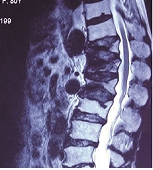

得了腰肌劳损怎么办?长期坐着办公,久而久之即可因姿势不良而引起腰肌劳损的发病率增加。坐着不动会造成腰部肌肉处于一定的紧张状态。出现酸胀感和疼痛不适感,并且使得腰部的支撑力和稳定性降低,容易受到损伤而产生急性腰痛发作,且迁延而成慢性腰痛的机会较大。那么,得了腰肌劳损怎么办?我们来看看专家的介绍吧。》》》网上挂号,立免专家挂号费